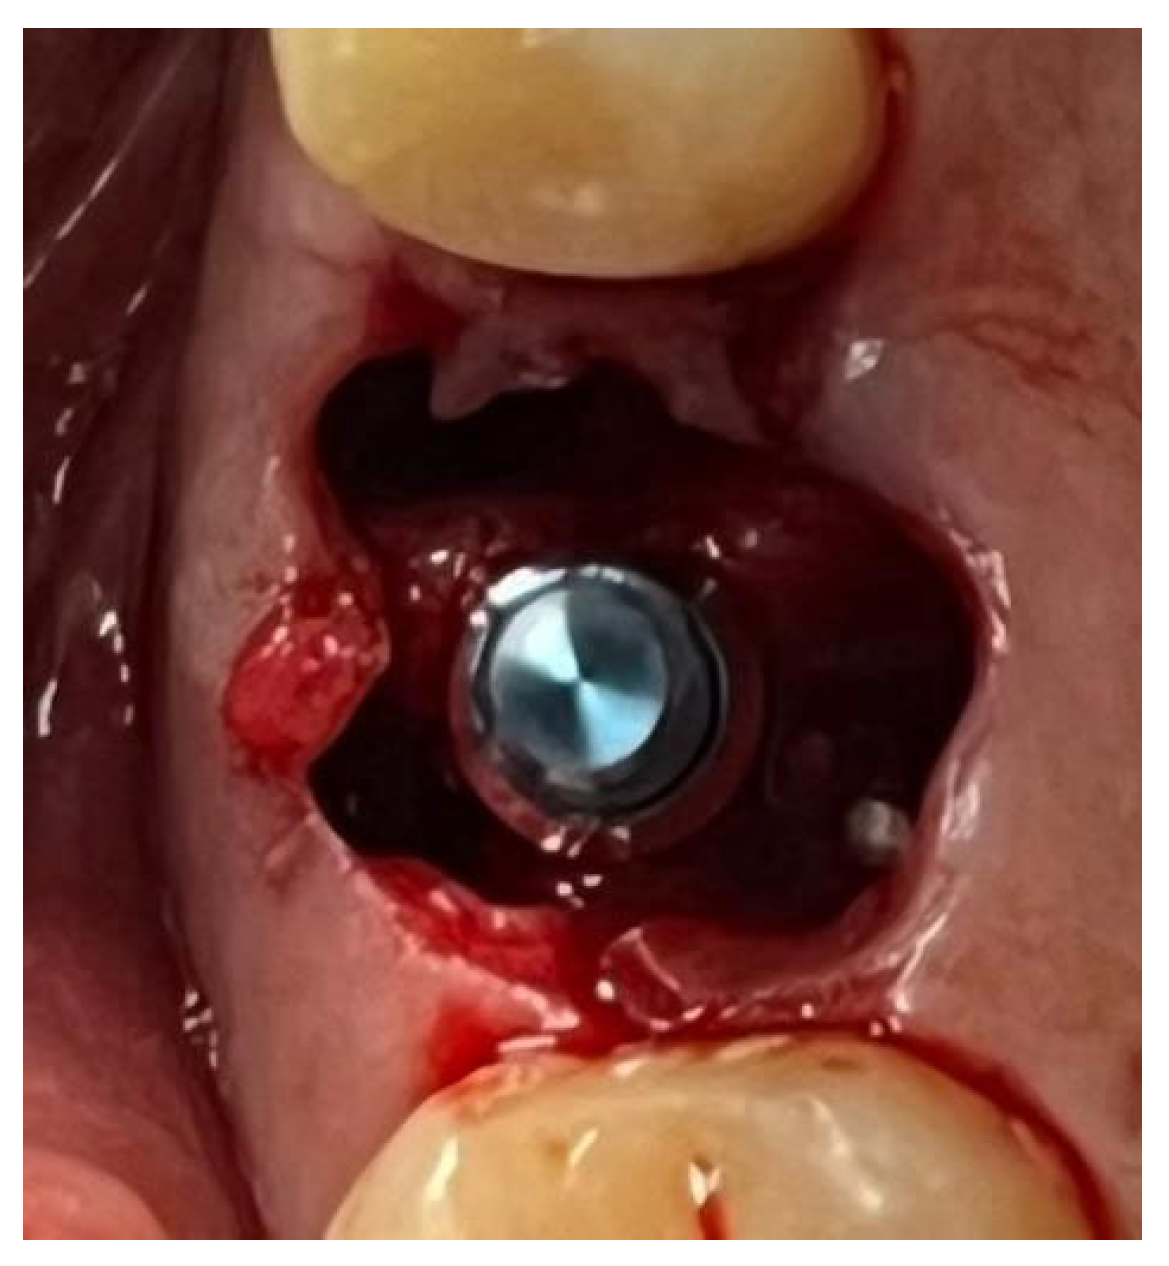

A similar technique was used in a 45-year-old patient with controlled hypertension, treated for the extraction of tooth 1.6 (Figure 11) and subsequent post-extraction implant-prosthetic rehabilitation (Figure 12). The surgical site was treated with bone graft material (Bio-Oss®—Geistlich), and a small amount of Glubran II was applied (Figure 13). Once again, Glubran II proved to be highly effective in stabilizing the graft material at the surgical site, providing excellent hemostasis and strong mechanical resistance from the film formed after polymerization (Figure 14).

Figure 12. Implant-prosthetic rehabilitation at the surgical site 1.6.